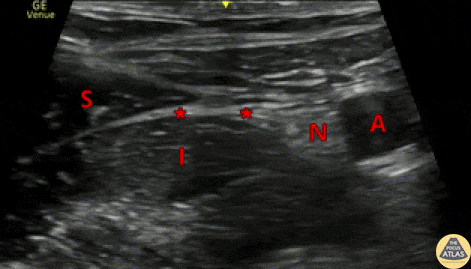

This clip shows the normal anatomy seen during a fascia iliaca nerve block. The image is obtained using a linear transducer in a transverse orientation over the middle to lateral third of the inguinal ligament. The probe marker is to the lateral aspect of the patient. The femoral nerve (N) is seen lateral to the femoral artery (A), and the sartorius muscle (S) is seen superficial to the iliacus muscle (I), with the fascia iliaca in between the two muscles. The target site for injection is just deep to the fascia iliaca, at a point lateral to the femoral nerve (*). Anesthetic should be visualized tracking medially toward the femoral nerve. Dr. Arian Anderson, PGY4 Denver Health Residency in Emergency Medicine